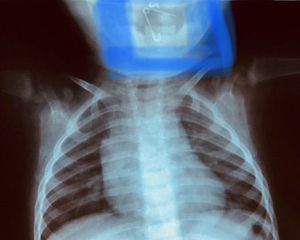

Patient 11 month ... mother consult only for sialorrhea ... taken xRay and... the girl had swallowed a clothes hook